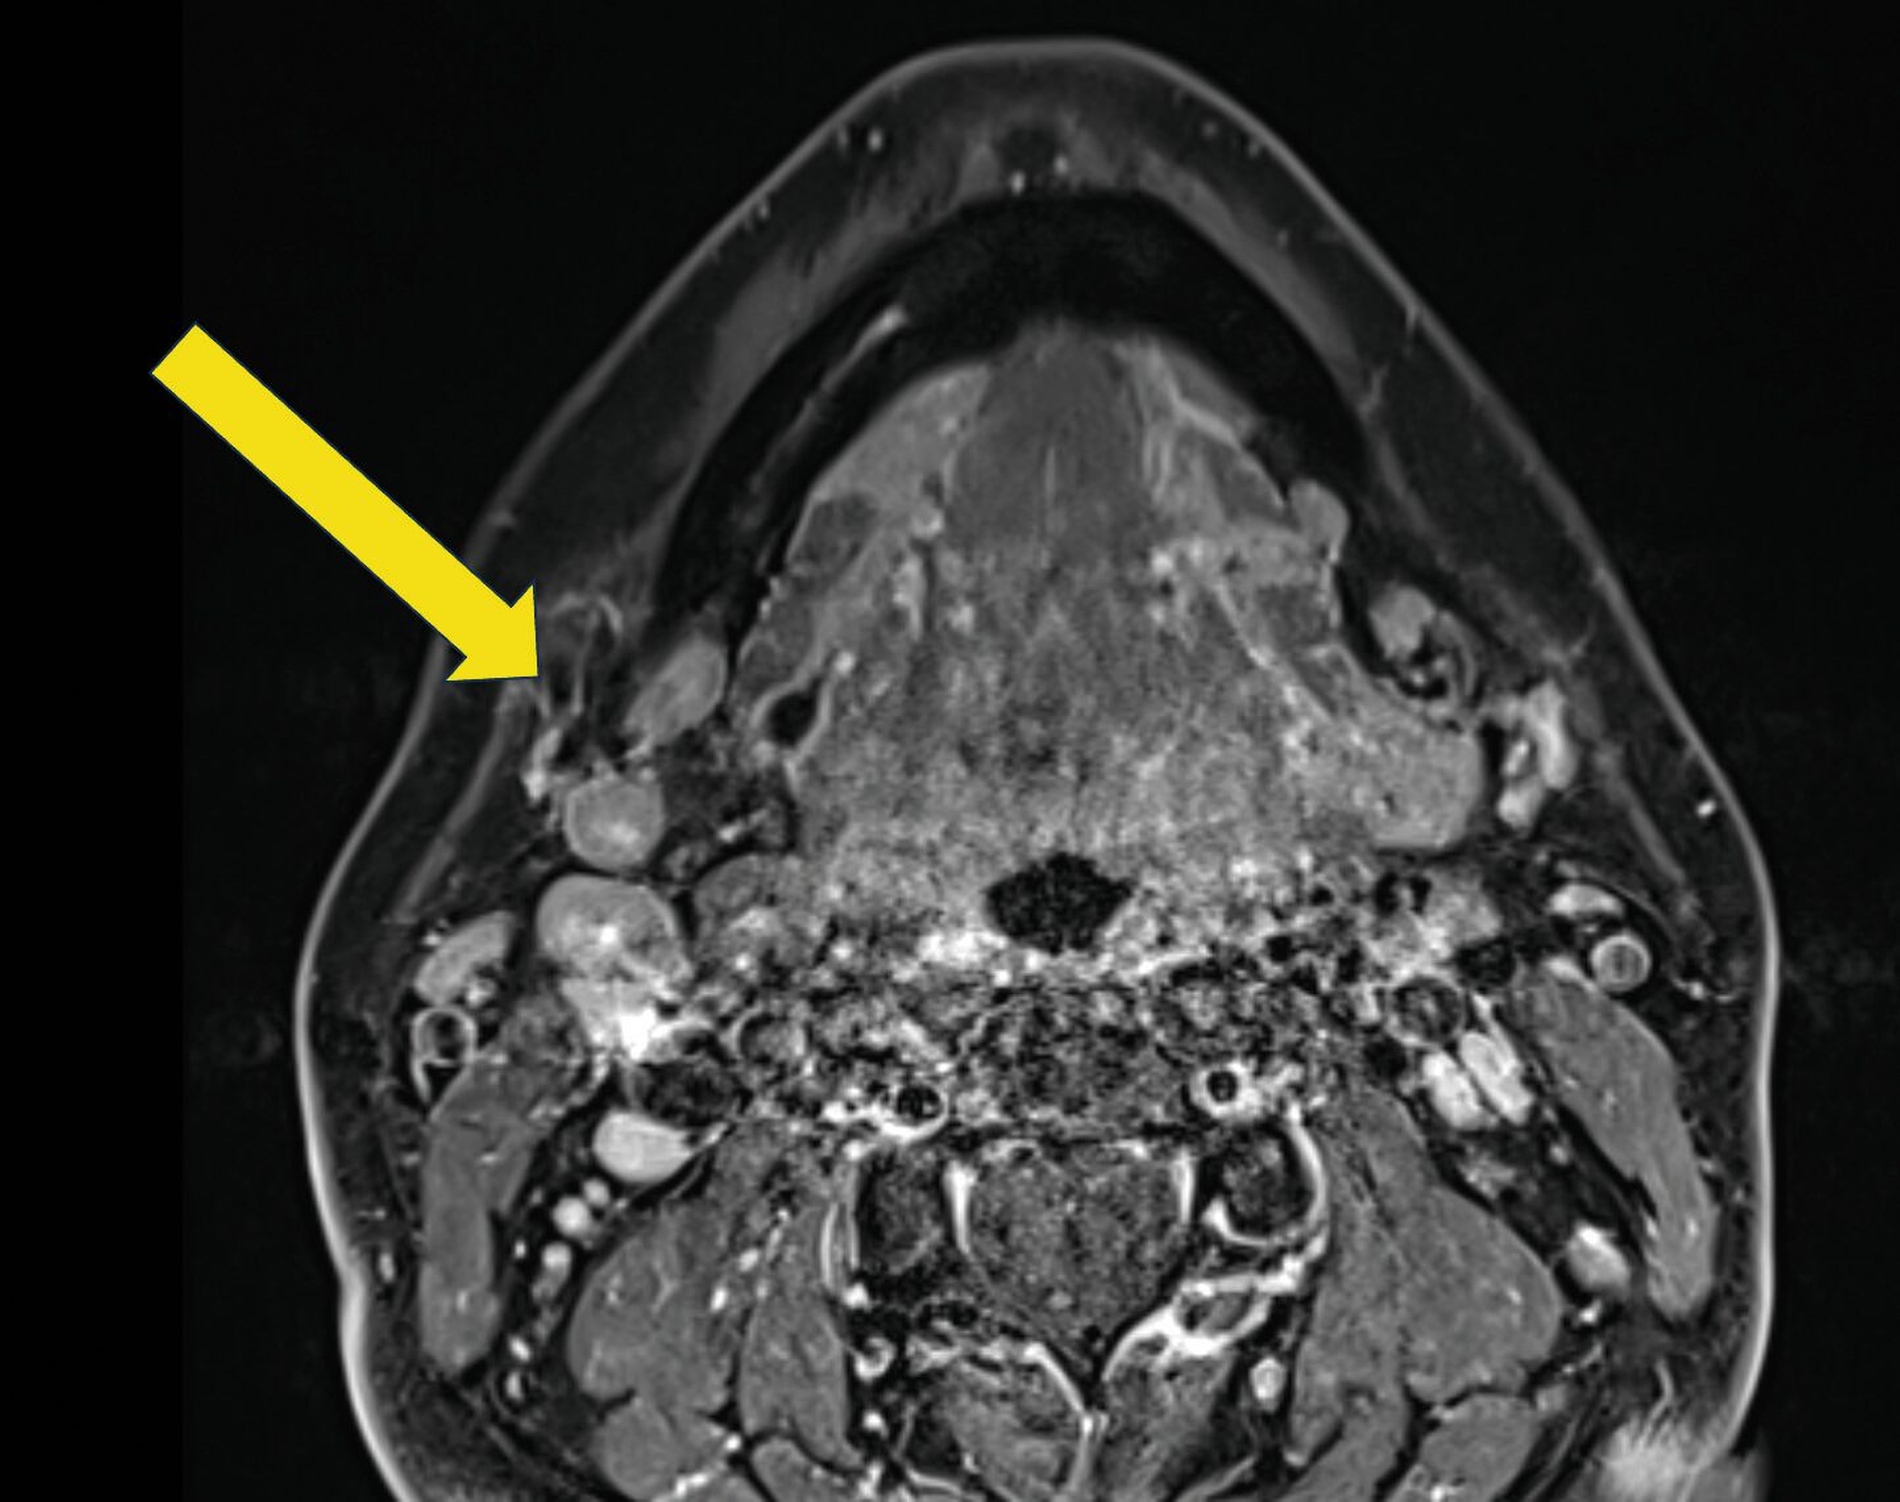

Zur weiteren Abklärung und Therapieplanung wurde eine Magnetresonanztomografie (MRT) durchgeführt, die lipotrophes Gewebe in der rechten Glandula submandibularis zeigte, begleitet von einer signalarmen Struktur von 6 mm x 6 mm x 4 mm im proximalen Ductus submandibularis (Abbildung 3). Somit wurde die Diagnose einer Sialolithiasis mit einem bis zu 6 mm großen Stein im proximalen Ductus submandibularis rechts ohne akute Entzündungszeichen gestellt. Die beobachtete Lipotrophie des Drüsengewebes wurde als Hinweis auf einen chronischen Prozess gewertet.